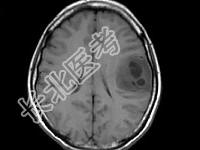

- 单项选择题女,33岁, 3个月前有右上肢及右颜面部麻木,伴耳鸣及头昏, 根据所提供图像,最可能的诊断是 ( )

A、脑脓肿

B、星形细胞瘤

C、脑结核

D、脑转移瘤

E、脑血吸虫病